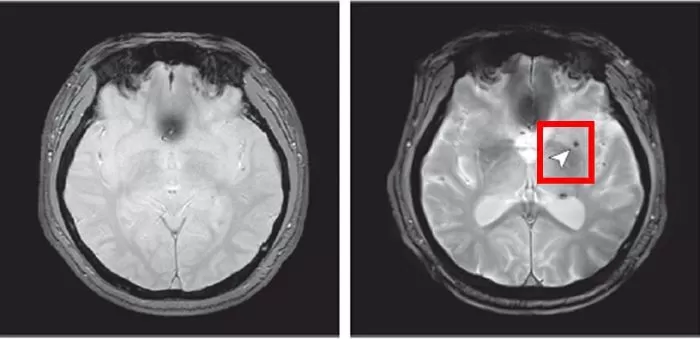

인사이트8년 후 뇌 미세출혈이 발생한 뇌영상 이미지 / 질병관리청

고려대 김난희 교수 연구팀의 분석 결과, 중등도 이상의 심한 폐쇄성 수면무호흡증 환자는 수면무호흡증이 없는 사람 대비 뇌 미세출혈 발생 위험이 약 2.14배 증가하는 것으로 나타났습니다. 반면 경증 수면무호흡증에서는 뇌 미세출혈 위험 증가가 관찰되지 않았습니다.